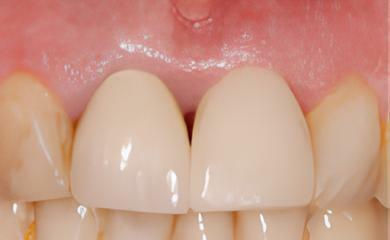

IMPLANTOLOGIE: LES IMPLANTS DANS LE SECTEUR ESTHÉTIQUE